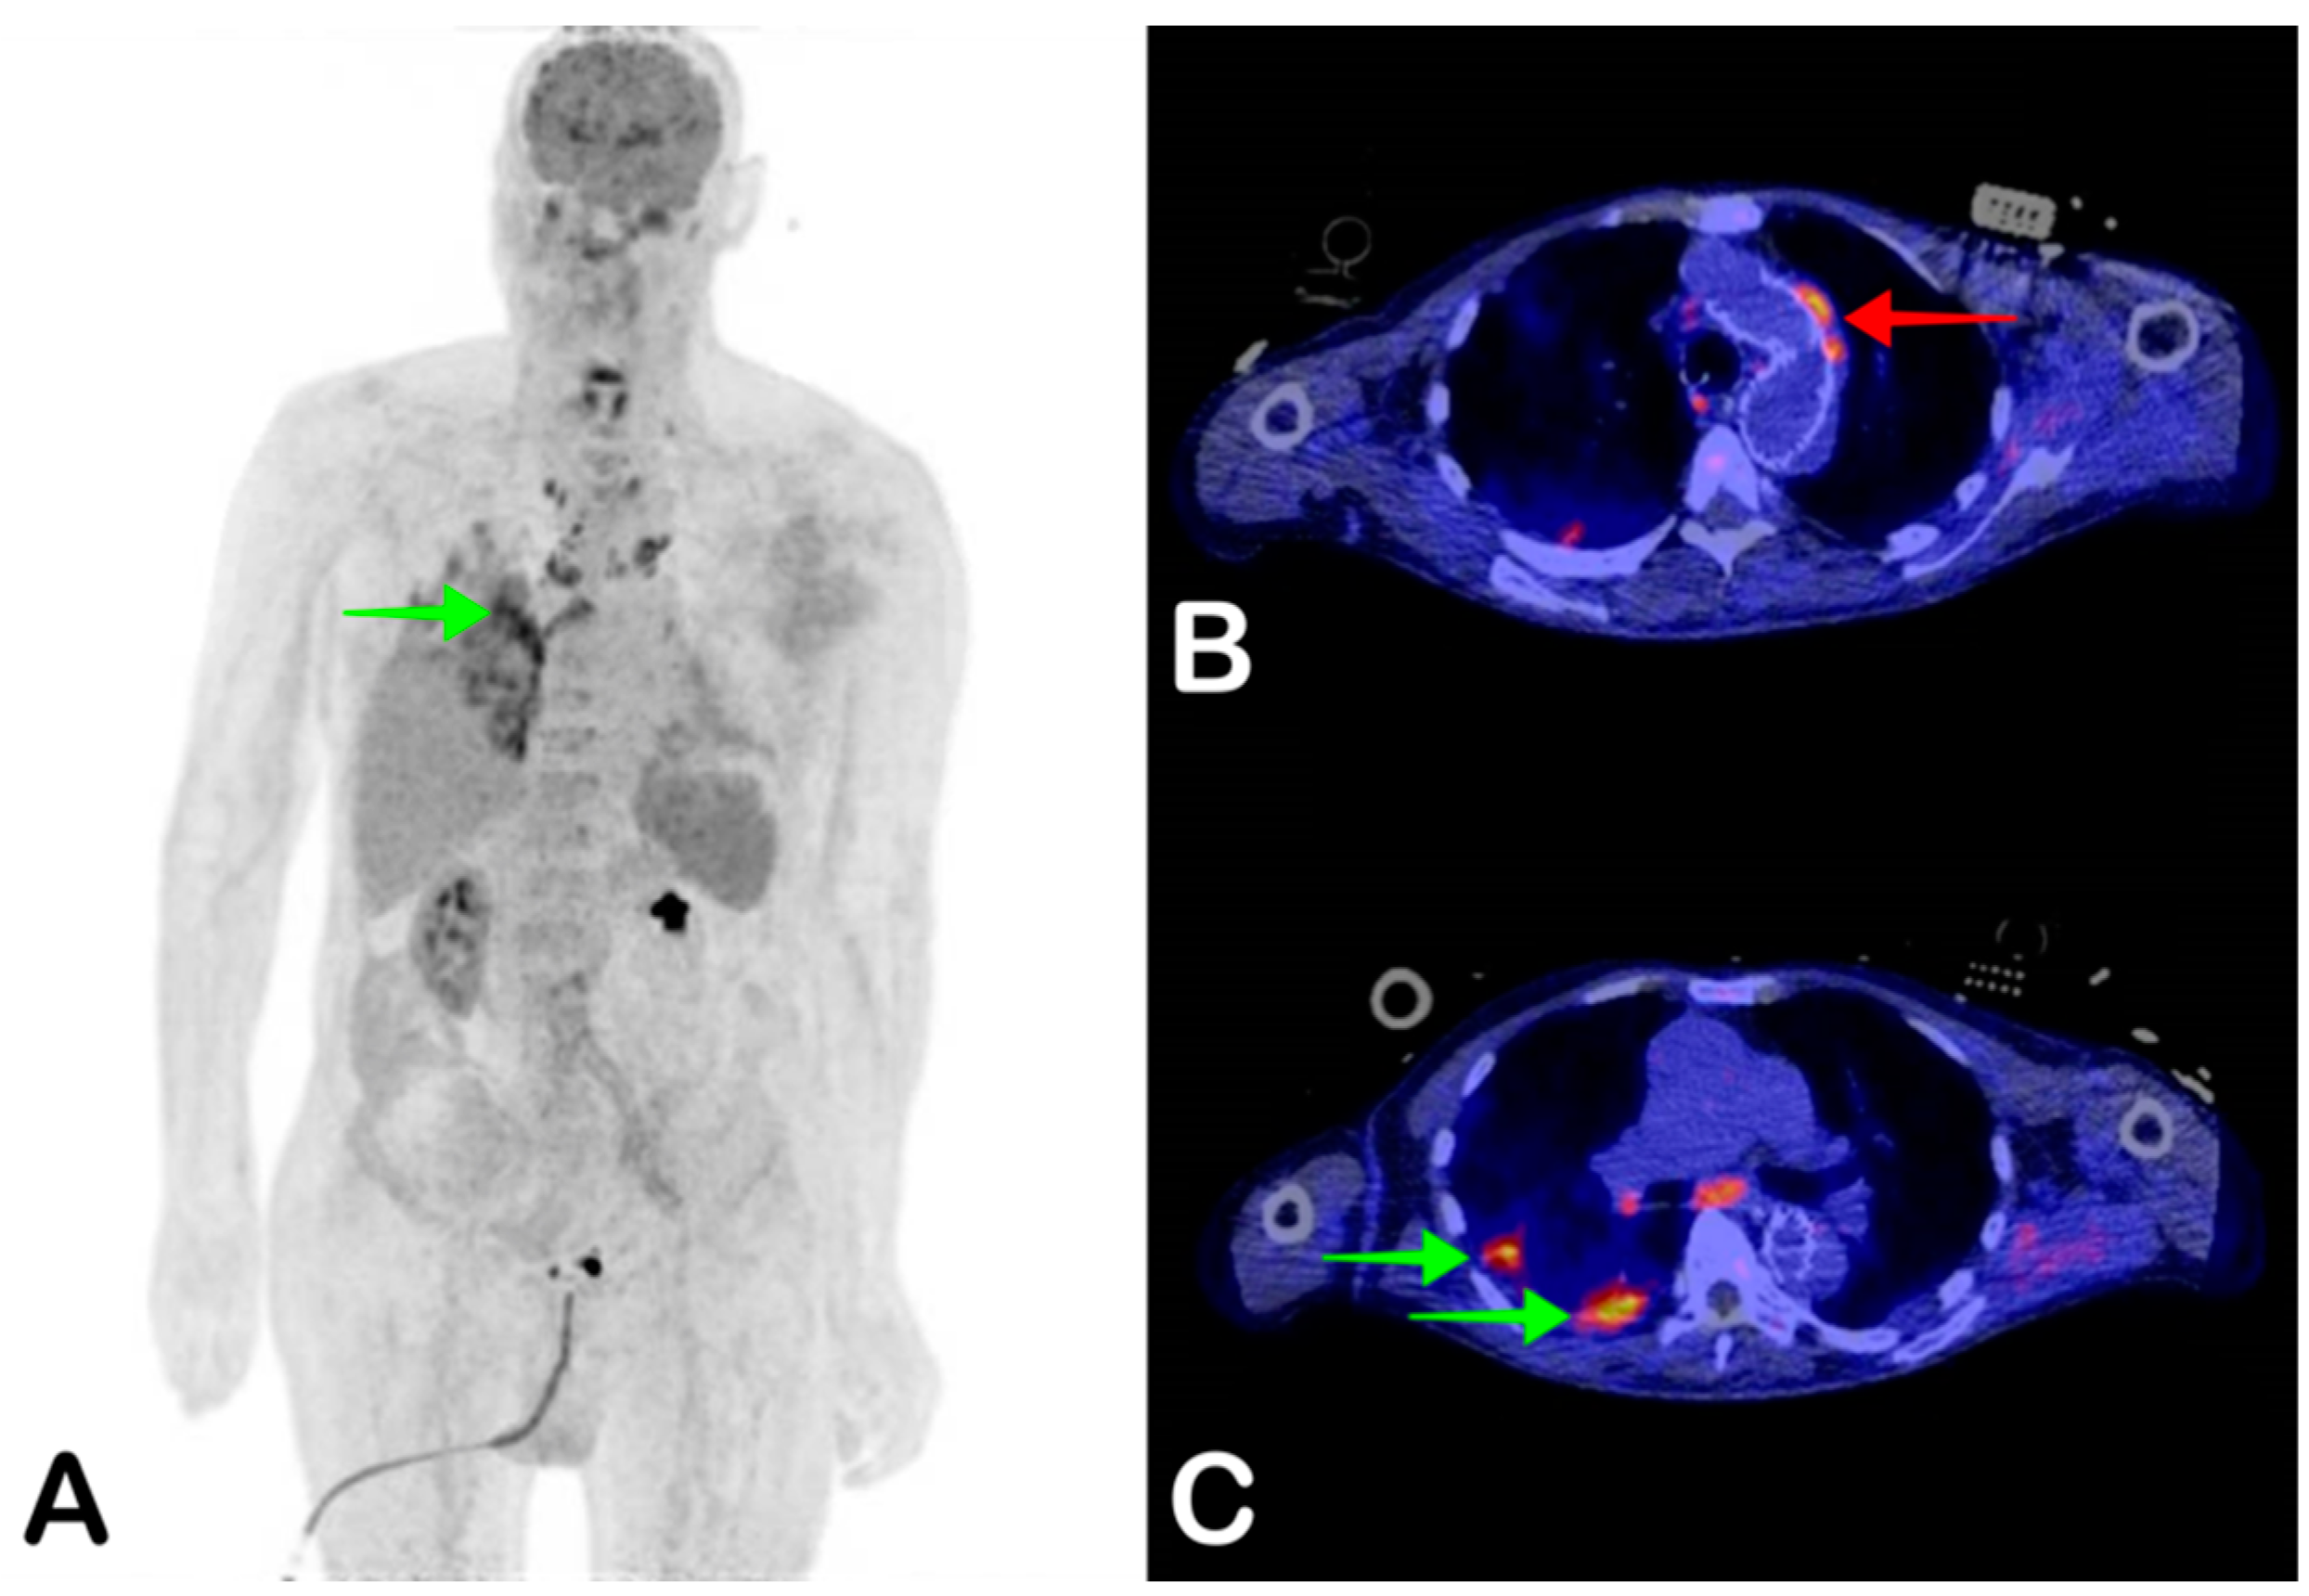

2.4. Vascular Graft Infection

- Chakfé, N.; Diener, H.; Lejay, A.; Assadian, O.; Berard, X.; Caillon, J.; Fourneau, I.; Glaudemans, A.W.; Koncar, I.; Lindholt, J.; et al. Editor’s Choice—European Society for Vascular Surgery (ESVS) 2020 Clinical Practice Guidelines on the Management of Vascular Graft and Endograft Infections. Eur. J. Vasc. Endovasc. Surg. 2020, 59, 339–384. [Google Scholar] [CrossRef] [Green Version]